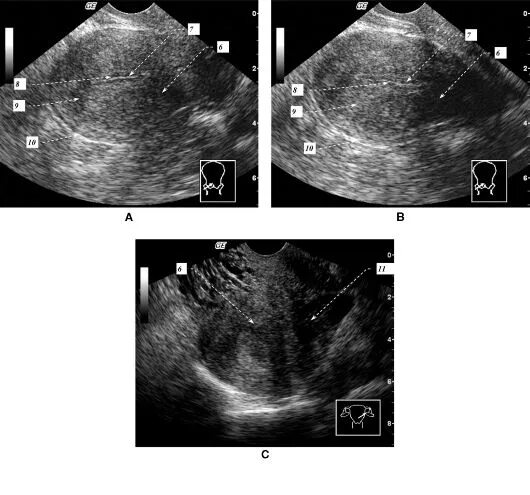

Диффузно неоднородно что значит